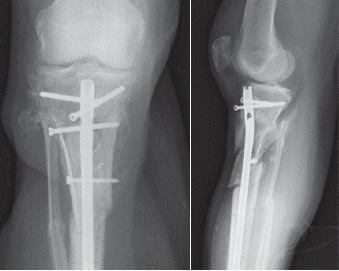

On the 12th day of admission the patient underwent open reduction and internal fixation (ORIF) with dual plate fixation using a two incision technique (Figure 4). After discussion at the multidisciplinary team meating, ORIF was favoured over external fixation as it was deemed that external fixation would not provide adequate ability to reduce the fracture fragments. In addition, the patient already had large fasciotomy wounds and so the advantage of a percutaneous frame had been lost. A plastic surgeon performed skin grafting, harvested from the patient’s thigh, to allow closure of his fasciotomy wounds immediately following ORIF.

Figure 4. Departmental X-rays 14 days after fixation with dual medial and anterolateral plate. Interfragmentary one-third tubular plates with unicortical screws had been used to aid reduction

After a period of three months, the patient’s antibiotics have been discontinued, however he remains on Fluconazole for at least another 6 months. Despite these challenges, the patient currently shows signs of recovery, mobilizing over short distances, weight-bearing with assistive aids and with healing wounds and early signs of callus formation on recent CT scans and plain X-rays (Figure 8, 9, 10). His inflammatory markers have improved significantly with a latest C-reactive protein of 14.7 from 250 mg previously (reference range 0-5) and normal white cell and neutrophils count.

Figure 8. Plain X-rays 3 months after removal of dual plate fixation with insertion of cerement V and intramedullary nail showing satisfactory alignment and early callus formation